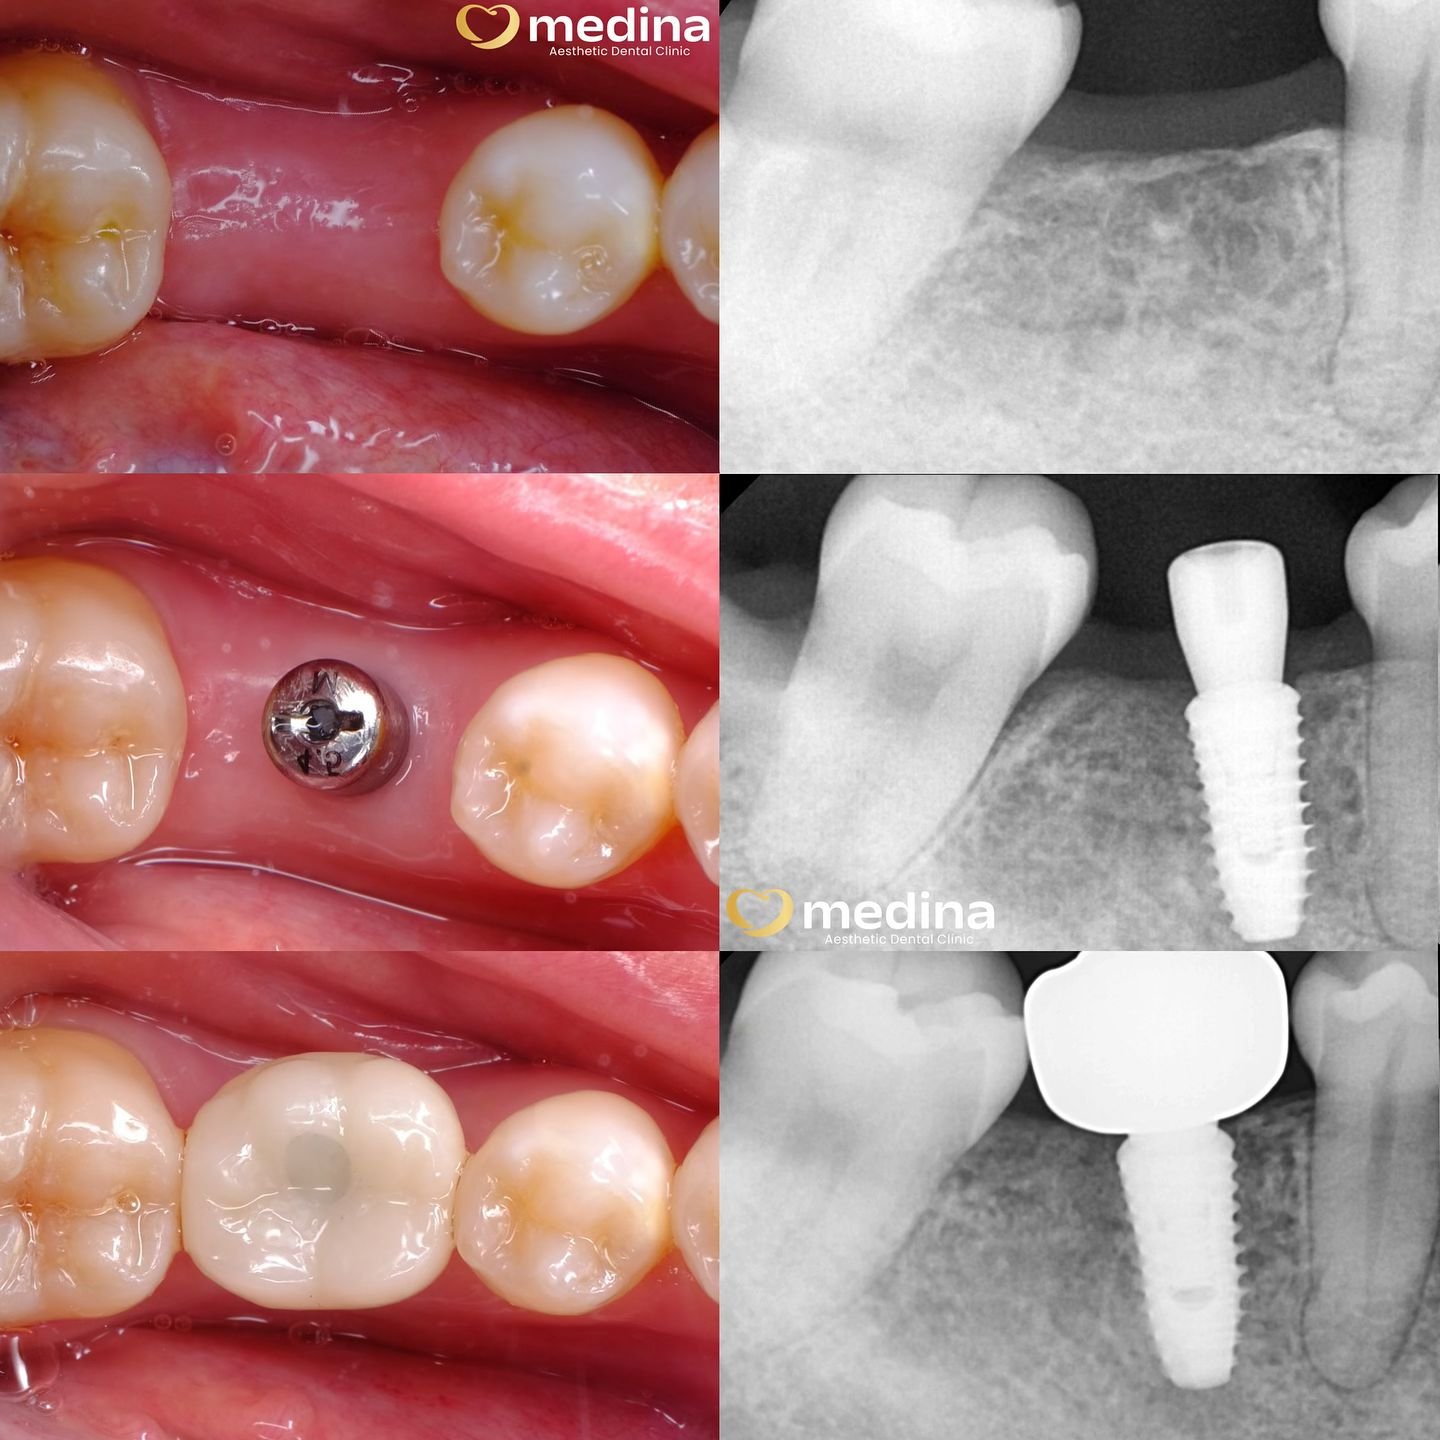

Implant adalah pemasangan gigi palsu menggunakan sekrup titanium (teknologi terbaik saat ini) didukung dengan alat rontgen/CBCT.